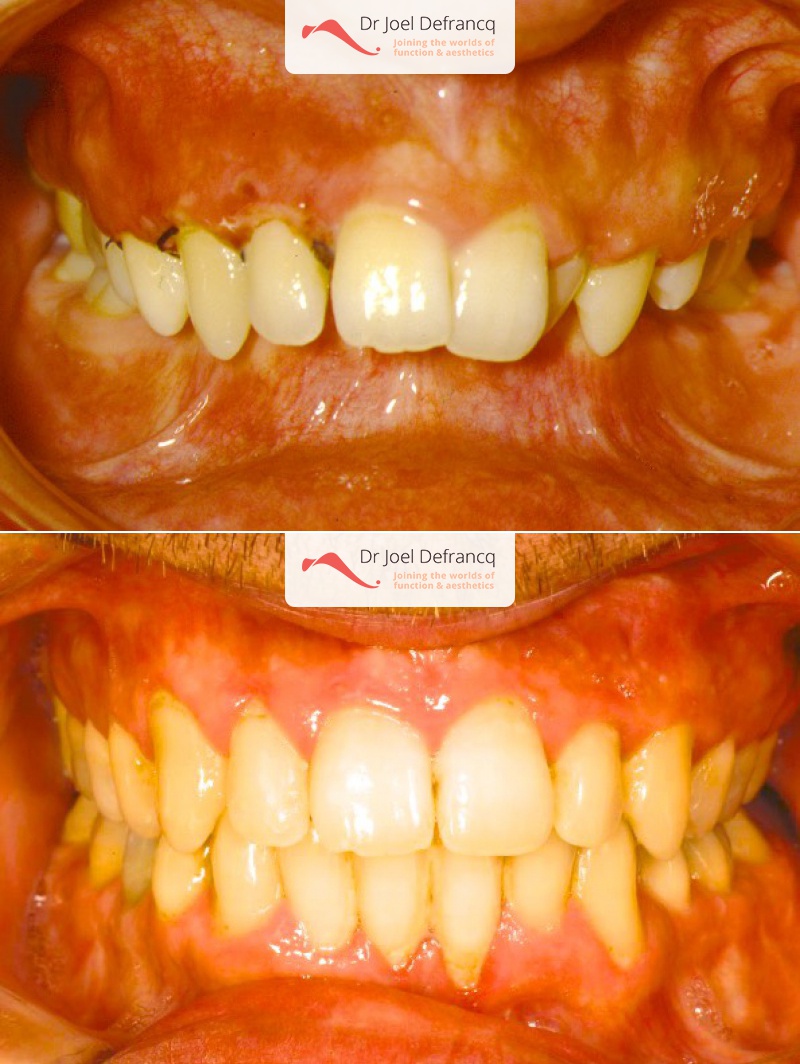

Kiro: Diepe beet, overbeet, diepe kin plooi

Diagnose van het gezicht

- Te kleine onderkaak (Overbeet)

- Te kort gezicht

Dentale diagnose

- Klasse II divisie 1

Kaakchirurgie

- Verlenging onderkaak (BSSO)

- Kinchirurgie